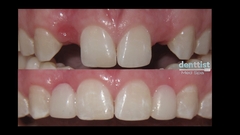

Galería Dental